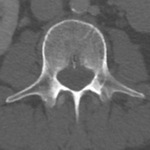

Spine

Axial